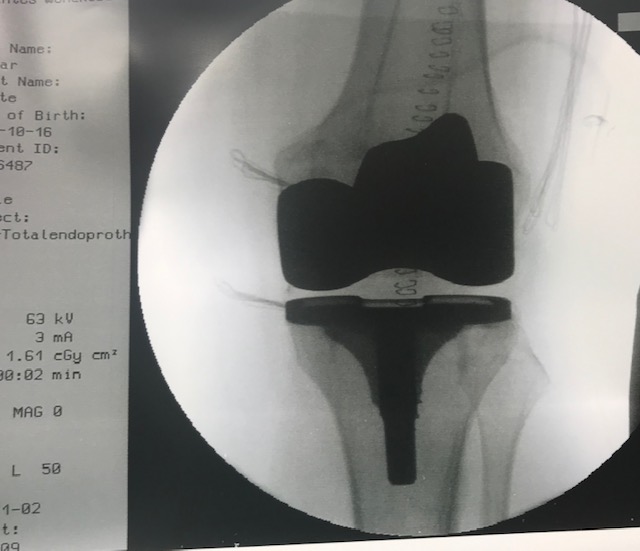

67 jährige Patientin mit Varus-Gonarthrose Stadium IV , starken Schmerzen , Geh-und Belastungsminderung und Einschränkung der Lebensqualitität

Präoperative Plannung der Knie-endoprothese mit einen speziellen Software

erfolgreiche Implantation einen oberflächenersatz Knieendoprothese durch Dr. Raslan unter Korrektur der Achse und Bandstabilität.

Foto-Quelle : Krankengut Praxis Dr. Raslan / Berlin